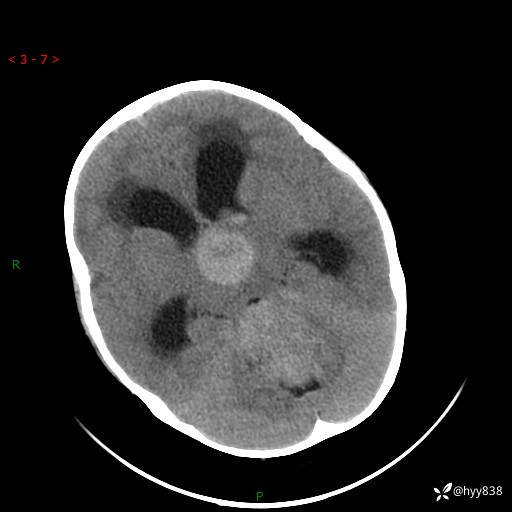

性别:女

年龄:3岁

简要病史:发现行走不稳2个月,加重1个月

颅脑CT平扫

三脑室、四脑室多发病变,如何分析?

髓母细胞瘤 (13)